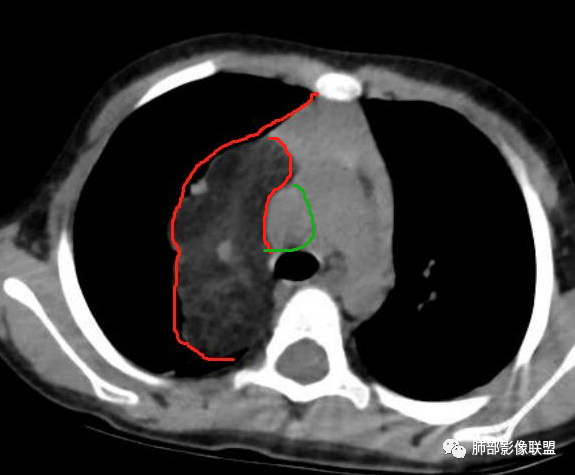

考虑纵隔脂肪瘤(黑虎纹),鉴别巨大胸腺增生(灰虎纹)。

右上纵隔混杂密度肿块,边缘光整,与纵隔分界清,其内多发脂肪密度,增强无明显强化,其内血管穿行,考虑纵隔脂肪母细胞瘤,鉴别畸胎瘤,脂肪肉瘤。

右纵隔团状,密度不均,脂肪密度为主,内可见腺体样组织,类似乳腺,病灶边缘有分叶,与胸腺关系密切,增强后血管穿行。考虑胸腺脂肪瘤(不典型垂乳征),鉴别畸胎瘤。

3岁儿童,右纵隔占位,内部间多发脂质成分及斑片状稍高密度影,考虑纤维成分,增强似有强化。病灶内血管未见明显侵犯,可考虑脂肪母细胞瘤,冬眠瘤等。

三岁小儿,右侧纵隔巨大脂肪密度肿块,肺动脉穿行其中,密度欠均匀,未见明确实性成分,纵隔脂肪母细胞瘤,冬眠瘤鉴别纵隔脂肪增多症(多弥漫对称)。

患儿3岁 咳嗽检查发现纵隔占位。右肺上叶受压表现,占位以脂肪组织密度为主,似见分隔,首先考虑为脂肪母细胞瘤,鉴别脂肪瘤,畸胎瘤。

幼儿,右上纵隔团块状脂肪密度影,边缘清晰,内可见血管及支气管穿行,考虑脂肪瘤,鉴别畸胎瘤。

幼儿,右上纵膈团块,脂肪密度,内见分隔,增强病灶内见血管穿行,结合患者年龄,考虑脂肪母细胞瘤,鉴别脂肪瘤。

纵隔畸胎瘤,右前上纵隔团状脂肪密度?粘液样密度为主病变,病灶软边缘有分叶,内可见分隔,增强后血管穿行。3岁。考虑纵隔脂肪母细胞瘤,鉴别畸胎瘤。

病灶属于交界区,主体位于肺内,占位效应明显,前方突入胸壁,胸腺受压变形,胸膜显示欠清楚;病灶包绕上叶肺动脉;似乎有体动脉供血。符合肺内的点:包绕上叶肺动脉分支;符合纵隔的点:前方似乎突入胸壁,与胸腺关系比较密切,但是与上腔静脉的关系提示病灶不支持纵隔来源,前纵隔的常规会将上腔静脉受压后移、外移,这是不符合的。

手术记录:见右肺上叶肿物,肿物与右肺上叶关系密切。与纵隔无粘连,逐步分离肿物,见肿物大小约6cm*5cm,边界清楚,于右肺上叶粘连,边界清楚,肿物包绕右肺上叶血管及支气管。超声刀逐步游离肿物,完整切除肿物,右肺上叶肺组织无破溃,表面无出血。

1.右上肺-纵隔交界区巨块影,主体位于右肺一侧,紧贴胸腺、头臂干、右锁骨下动脉、上腔静脉、奇静脉等,不能分离,但病灶整体边界清楚。注意上述相邻腔静脉等结构未见受压变形,纵隔亦未见明显向左推移,至少提示两点:

2.肺动脉穿行也许是肺内来源最重要支持点!

CT扫描对脂肪类肿瘤常有独到价值。肿块孤立、边界清楚,未见周围浸润,较均匀脂肪样低密度,高度提示为良性!

发生于成人为脂肪瘤表现,婴幼儿自然会想到脂肪母细胞瘤。两者生物学行为并无本质区别。